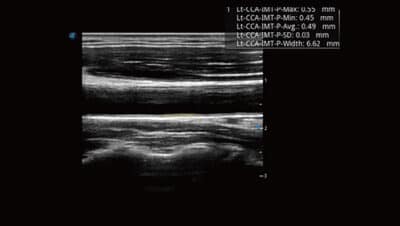

Automobil IMT

- Inteligentní nástroj pro analýzu potenciálního rizika kardiovaskulárních onemocnění.

- Jedním kliknutím tlačítka můžete změřit přední i zadní tloušťku intimy společné krkavice.

- Tento jednoduchý postup zvyšuje produktivitu vyšetření a zvyšuje diagnostickou hodnotu vyšetření.